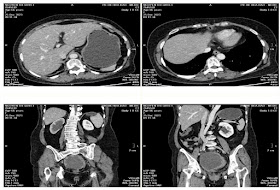

MSCT represented an 9x10 cm ovarian tumor and vegetations in the pelvis which caused the hydronephrosis .